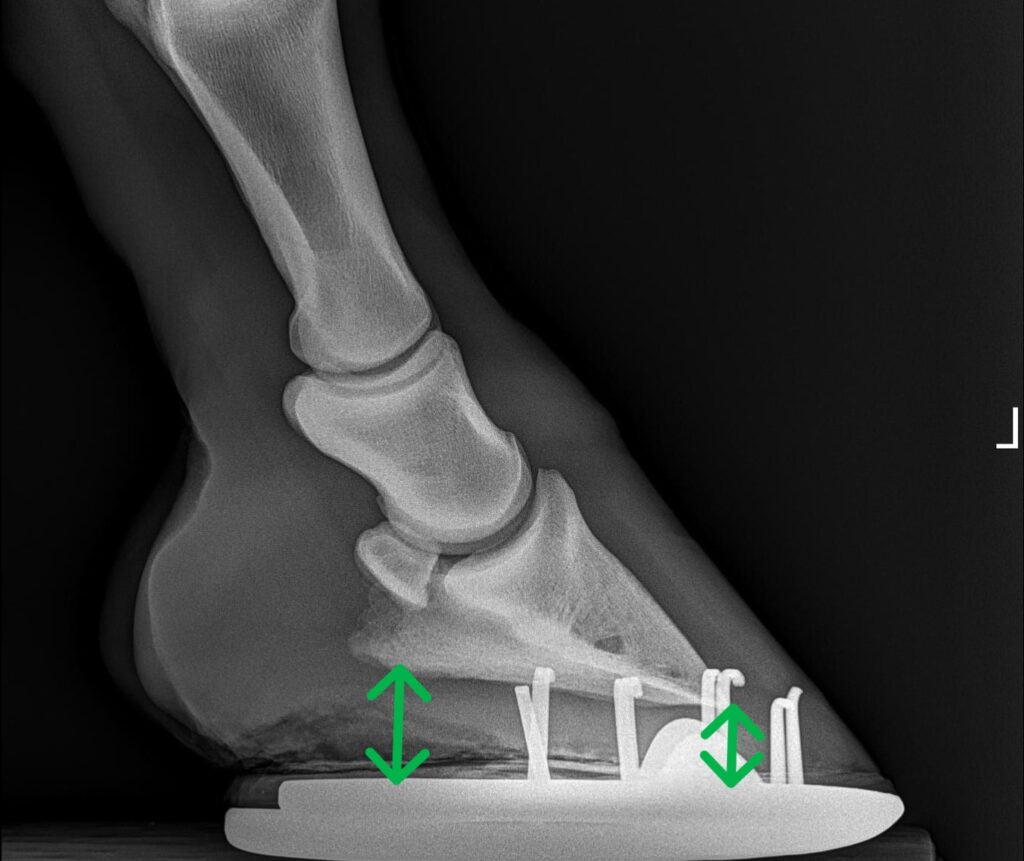

- Negative palmar foot angle is relatively common in warmbloods. The pedal bone, or PIII, is the bone inside a horse’s hoof. It is generally thought that the bottom surface of this bone should be at two to seven degrees relative to the ground surface. This creates a slightly toe downward angle and provides the horse with optimal balance and push off the feet, especially the hind legs. Horses with flat to negative palmar foot angles have a PIII bone that is elevated at the cranial edge (toe) and lower at the caudal edge (heel). These horses are essentially standing and moving from a “rocked-back” position, which places additional stress on the hind leg (high suspensory ligaments, hamstrings and gluteal muscles) and on the SI joint area.